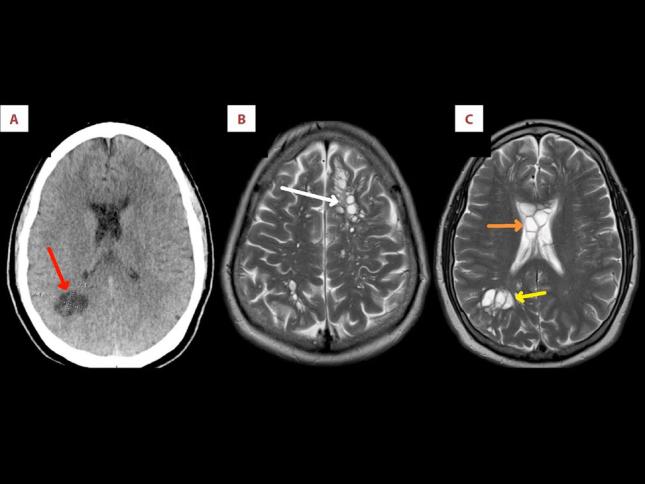

جهان خوردن گوشت خوک نیمپز مردی را به انگل مغزی مبتلا کرد عکسبرداری از جمجمه این مرد تعدادی کیست در قسمت ماده سفید مغز نشان داد عفونت قارچی مغز در فیلمهای آخرالزمانی؛ بیماری مرموزی که در کمین است علت عجیب سردرد هفت ساله زن استرالیایی دانشمندان چینی سویه جهشیافتهای از کرونا ساختهاند که به مغز حمله میکند